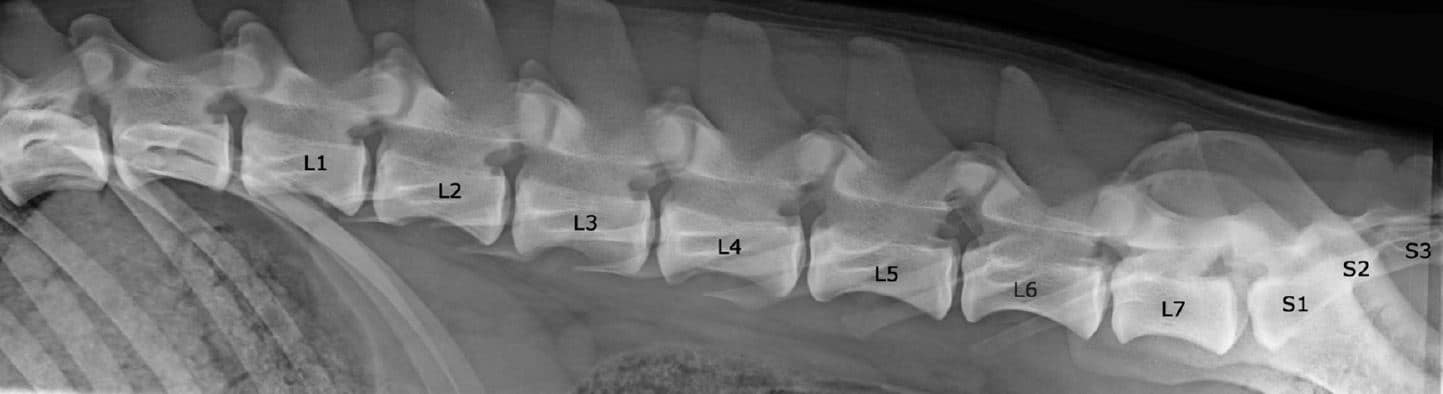

NORMAALI SELKÄRANKA

Koiran normaali selkäranka koostuu seitsemästä kaulanikamasta (C1-7), kolmestatoista rintanikamasta (T1-13), seitsemästä lannenikamasta (L1-7) ja kolmesta ristinikamasta (S1-3). Nikamien laskenta aloitetaan ensimmäisestä rintanikamasta (T1). Häntänikamien CD) määrä vaihtelee.

Ristiluu yhdistää lannerangan lantioon. Se on osa lantiota, joka sijoittuu lannerangan ja hännän väliin. Lonkkaluiden väliin asettuva ristiluu on vahva ja kolmiomainen muodoltaan. Normaali ristiluu koostuu kolmesta yhteenluutuneesta nikamasta; S1, S2 ja S3.